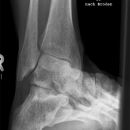

Brodenaufnahme

Diente früher zur Beurteilung des hinteren, unteren Sprunggelenks. Mittlerweile durch CT verdrängt.